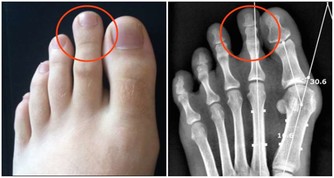

此種疾病多發於40歲以上人群,且女性病發率相對更高一點,而三叉神經痛屬於腦神經疾病,三叉神經痛之所以會引起牙痛,與三叉神經的分佈有很大關係。

它主要分佈於臉部,而三個點的其中兩個點,就是位於上頜和下頜,當三叉神經出現病變後,也就可能會觸發到上下頜,從而引發牙痛。

牙痛的現象,表現更為強烈,也是可能會受到上下頜活動的影響,比如說吃東西、打噴嚏、大笑、耳朵癢這些情況,都可能會讓牙痛的感覺更為強烈。